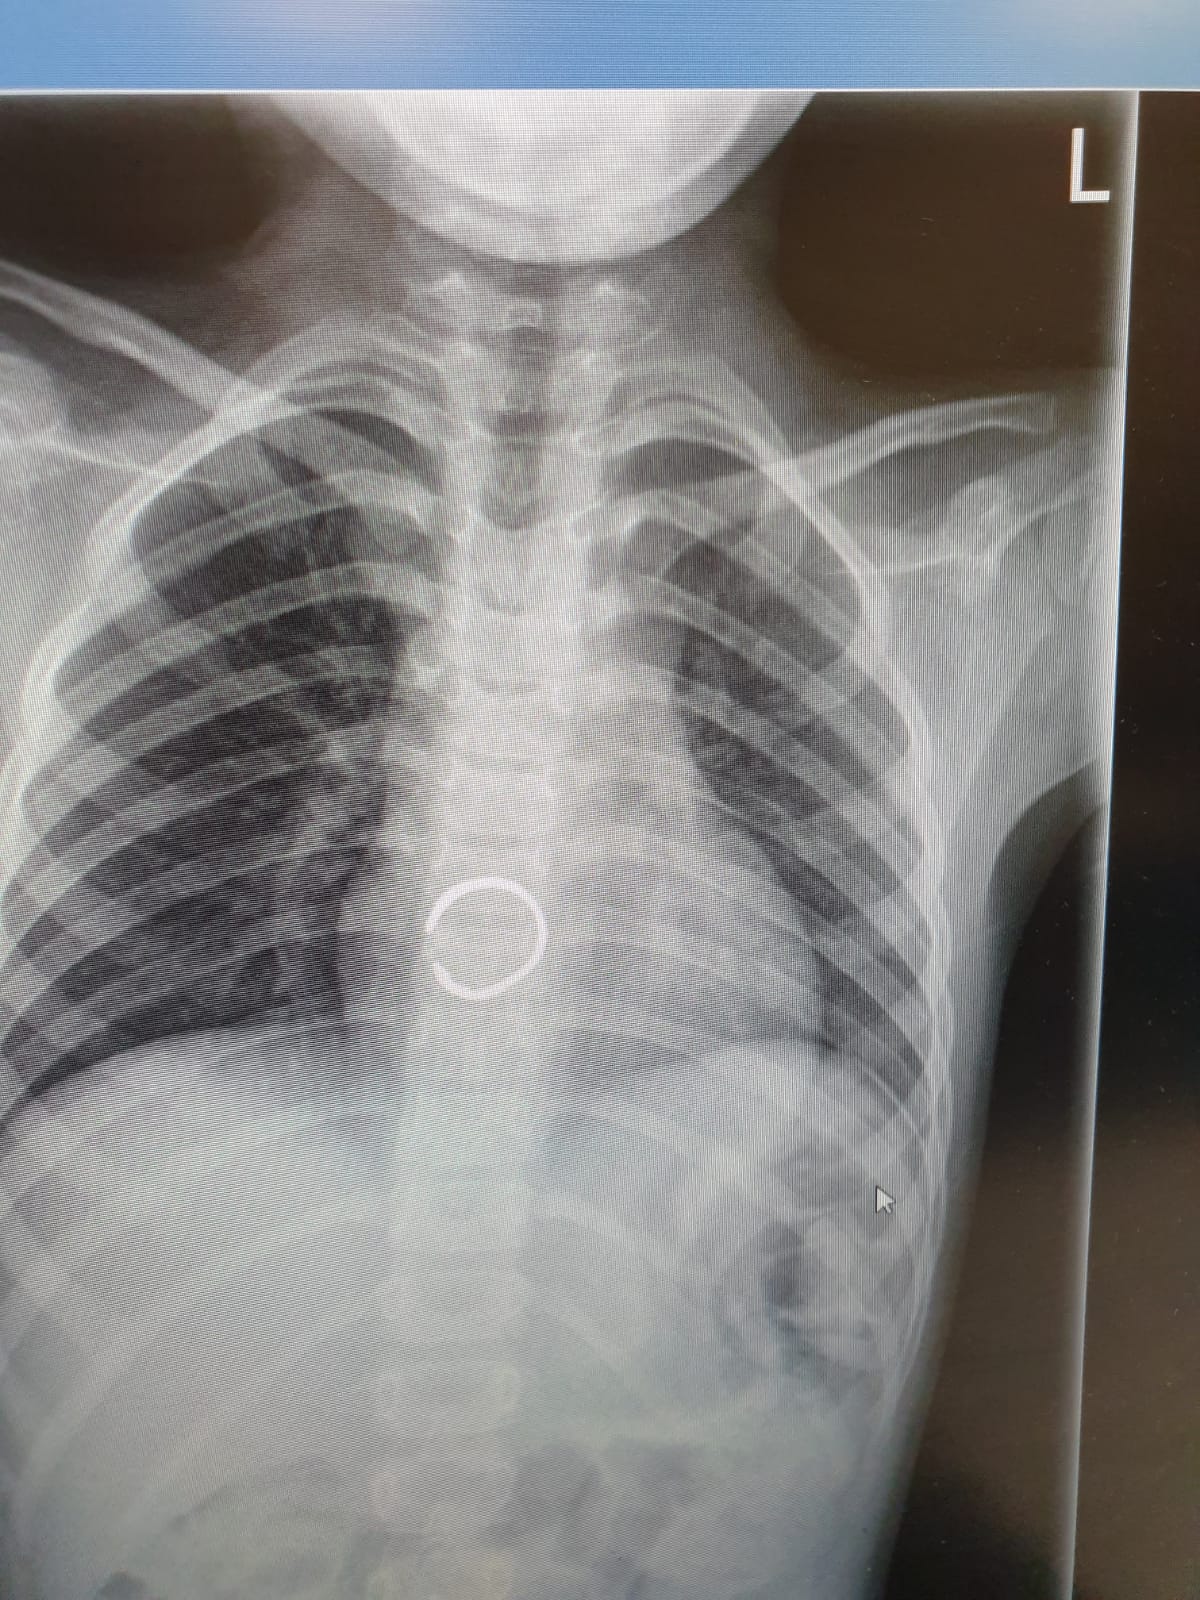

שירה, כך על פי הדיווח שקיבלו הצוותים הרפואיים ב'זיו', בלעה את הטבעת שמצאה בגן הילדים בו היא לומדת. לאחר שהיא חשה כאבים באיזור החזה, היא הובהלה לבית החולים, שם בוצעו צילומים ולאחר שהראו כי הטבעת נתקעה בושט, הוחלט לבצע פעולת גסטרוסקופיה בהרדמה מלאה להוצאתה.

בשל היותה של הטבעת חתוכה, נדרשה תשומת לב גדולה יותר ורמת דיוק גבוהה, על מנת לא לפצוע את הנתיב החוצה.